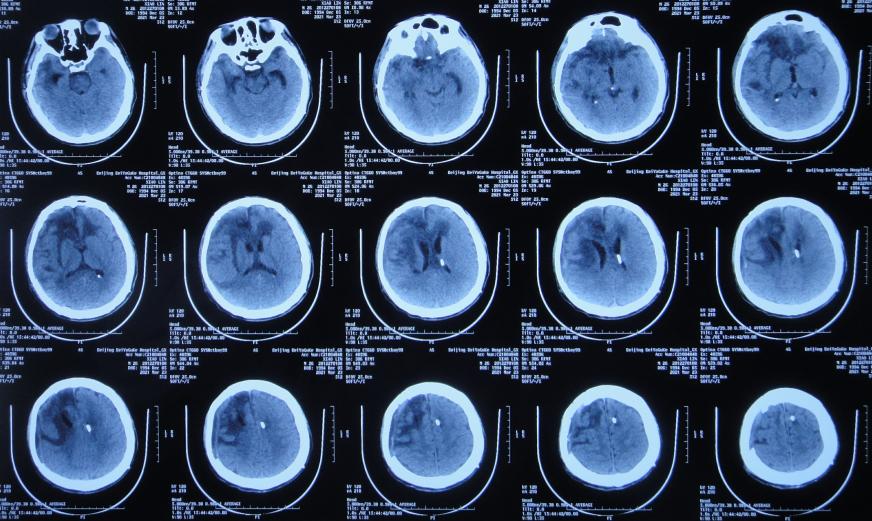

患者于2020年12月12日,在工作时意外从货车上摔下致头颅受伤,出现意识不清,送至河北省定兴县某医院,急诊查头颅CT示颅内血肿,中线有偏移( 图-1 ),给予开颅颅内血肿清除术+去骨瓣减压术,留置引流管,并行气管切开术;术后当天查头颅CT示开颅术后状态( 图-2 ),转入ICU病房。

图-1: 2020年12月12日头颅CT

图-2: 2020年12月12日开颅术后头颅CT